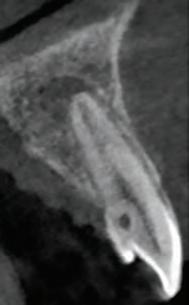

In order to proceed with the digital planning workflow, a series of clinical records were made, which included pre-operative radiographs, clinical photographs and digital intra-oral scans (3Shape; TRIOS, Copenhagen, Denmark). A photorealistic 3D tessellation, or triangulation, of the facial features was generated in real colours using the Face Hunter scanner (Zirkonzahn Srl; Gais, Italy), while patient-specific occlusal information was captured and recorded using the PlaneSystem (Zirkonzahn Srl; Gais, Italy) (Figure 3). When combined, these records allow for efficient communication from the clinic to the dental

laboratory, regarding the precise spatial arrangement of the pre-operative dentition as it relates to key aesthetic and biomechanical determinants of a harmonised tooth arrangement,9 including:

1. The facial mid-line: this in turn determines the ideal dental mid-line location.10

2. The inter-pupillary line and natural head position: this determines the ideal occlusal plane of the maxillary anterior teeth as viewed from the patient’s front.11,12

FIGURE

3. The smile display: this is a determinant of the incisal edge positions and therefore the ideal tooth lengths and gingival margin locations when viewed from the patient’s front and side profiles.13

4. The ala-tragal line: this is a key determinant of the maxillary occlusal plane as viewed from the patient’s side profile.14

5. Maxillo-mandibular relationships: from which incisor inclinations and interarch static and dynamic occlusal factors may be determined.15

FIGURE 3: Identification of the ala-tragal line with black marker in preparation for recording of occlusal-specific information using the PlaneSystem. Threedimensional facial tessellation scanning, achieved with Face Hunter, permits merging of an intra-oral scan using Zirkonzahn.Modifier software. Key biomechanical and aesthetic landmarks are now conveniently available for reference at the dental laboratory.